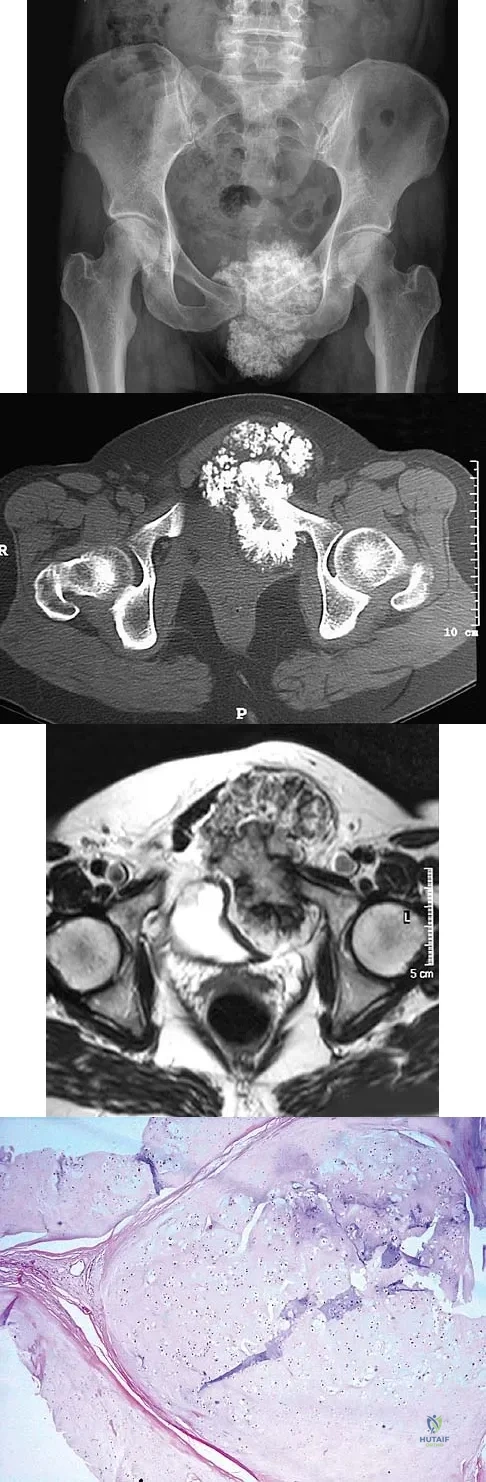

Question 93

A 47-year-old woman has an asymptomatic pelvic mass that was discovered on routine gynecologic examination. A radiograph, CT scan, MRI scan, and biopsy specimen are shown in Figures 7a through 7d. Metastatic work-up is negative. Treatment should consist of

Explanation